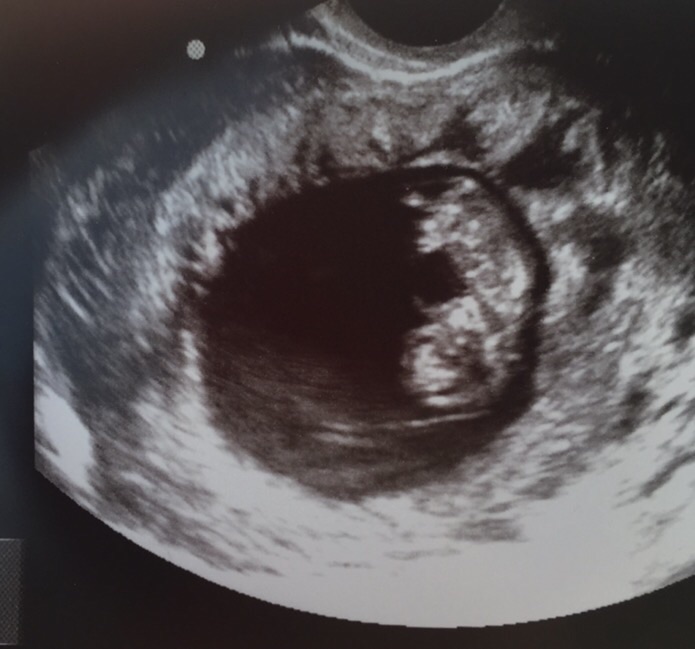

Had another u/s done yesterday due to some bleeding during sex. Baby is great and right on schedule 7 weeks 2 days...can't wait for my next one on the 29th!!